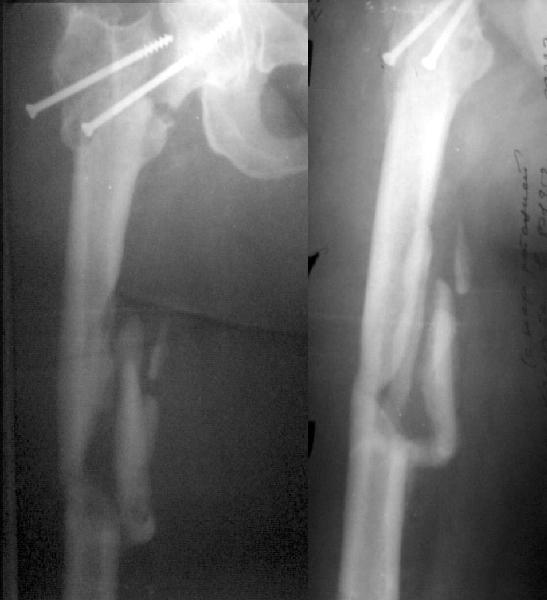

Примерно год назад женщина 44 лет оперирована по поводу перелома шейки и диафиза бедра через 2 нед. после автоаварии. Сделали закрытый остеосинтез бедра стержнем и попытались синтезировать шейку мимо гвоздя.

Пролучилось плохо (снимок N1, через 1 мес. после операции), отчасти благодаря тому, что окружность бедра в верхней трети у нее больше 80 см. Гвоздь на днях удален через старые разрезы. Шейка, понятное дело, не срослась, а диафиз - только на ограниченном участке (снимок N2).Встает вопрос - что делать дальше? Думаем про вальгизирующую остеотомию с фиксацией клинковой пластинкой. Может быть, с ретроградным штифтованием бедра (хотя места между переломом и нижним концом пластинки маловато). Эндопротез с длинной ножкой не доступен. Ожирение - прежнее. Заранее спасибо.

This is a good example of sub optimal placement of the neck screws. Young patients with neck/shaft combo fxs have a high Pauwells' angle. This is counteracted by open reduction and internal fixation in order to reduce caudal portion of fem neck. The screws are angled differently by placing them perpendicular to the fem neck fx line (typical AO technique) or horizontal to the floor. The screws here are similar to elderly fem neck fx types. Therefore, no biomechanical advantage exists and the nonunion is produced.

You need to perform a valgus osteotomy with 130 osteotomy plate. This will improve the relative Pauwells' angle and improve the union rate. Problem is the probable nonunion or partial union to the shaft. The osteotomy plate is

only made with 6 holes which will not allow for bypassing the shaft problem.

You will probably require an open plating and bone grafting. Try to angle your distal ost and prox shaft screws so that they overlap and theoretically decrease the stress riser created with the double plates.

Сделали подвертельную вальгизирующую остеотомию (чуть низковато плучилось), синтезировали клинковой пластинкой. После компрессии и

латерализации винтом ниже остеотомии, нижний винт в пластинке заменен на 3 монокортикальных. Бедро ретроградно рассверлили и заштифтовали UFN 12 мм, верхний запирающий винт ввели через пластинку. Псевдартроз сдавился хорошо. Снимок в приложении. Буду рад услышать комментарии.

The valgus osteotomy has improved the position of the femoral neck fracture

:-)

The blade plate is in the anterior and proximal aspect of the femoral head

:-(

What activity level is planned? Keep a close eye on the femoral head and neck. They will determine outcome, primarily.